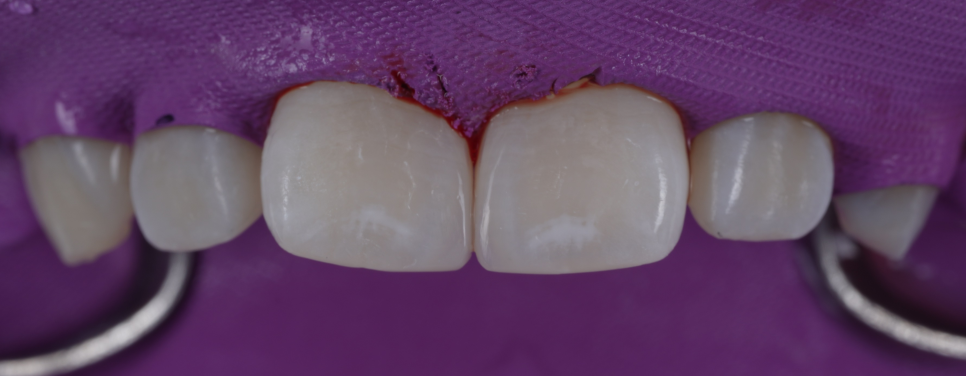

그래서 여러 각도에서 확인해 보며 양쪽 치아의 길이와 곡선을 최대한 똑같이 맞췄어요.

마무리하기 전, 환자분한테 최종 모양을 확인받았어요.

촬영 : 251030

마지막으로 거친 표면을 매끄럽게 다듬고 광택을 내면서 빛이 고르게 반사되도록 마무리했어요.